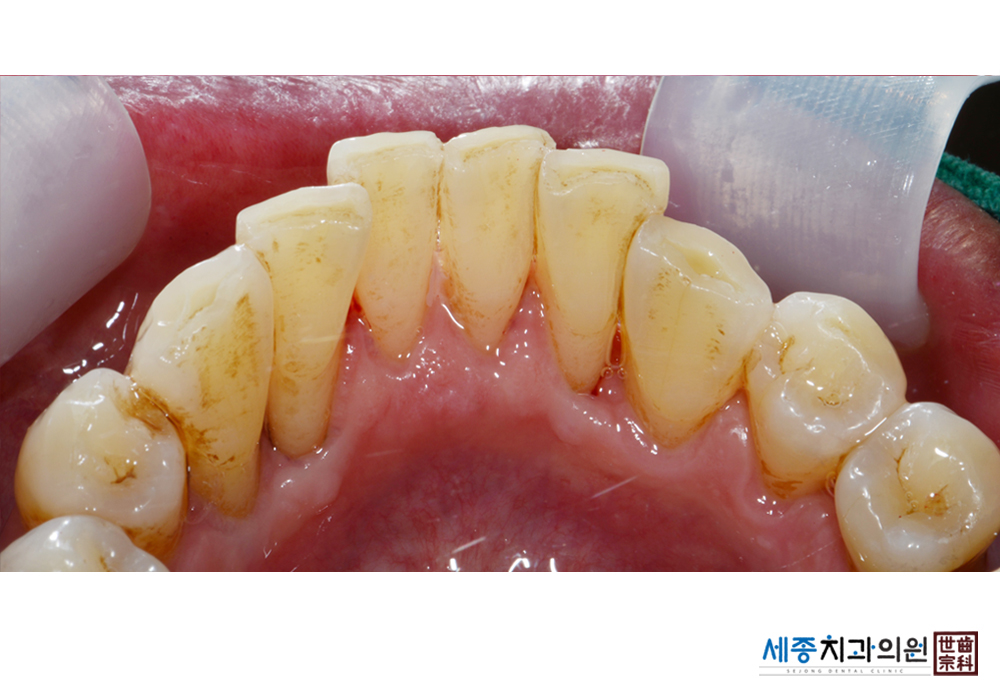

[스케일링] 치주질환 예방 스케일링

치료전 : 2022-05-04

치료후 : 2022-05-04

가글마취&저주파 스켈러를 사용한 스케일링